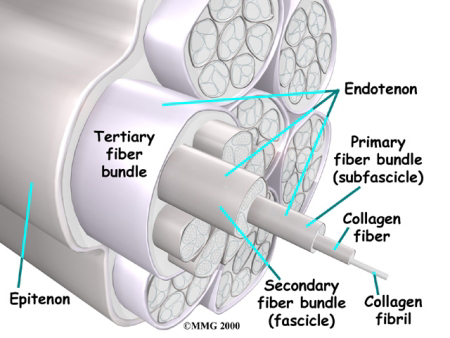

Tendons connect muscle to bone. A tendon is made of material called collagen. Collagen is a key building block of the body. Collagen is considered a connective tissue because it forms tough strands that are like the strands of a nylon rope. Like the strands in a rope, the strands of collagen line up. The more strands, and the better they line up, the stronger they are. The tendon is wrapped in a thin, slippery covering called the tendon sheath. The tendon sheath allows the tendon to slide easily against the tissues around it.

Aging seems to cause tendon damage in some cases. As we age, the tissues of the tendon can break down, or degenerate. Age-related tendon problems do not seem to cause inflammation. The tendon material itself is more affected in these conditions and some surgeon's refer to this type of tendon problem as tendonosis.

Some researchers think that a decreased blood supply to the tendons can cause the tendon damage in tendonosis. The decreased blood supply does not allow the tendon to get enough oxygen from the blood. This leads to a condition where the tendon degenerates. The collagen material that makes up the tendon actually becomes weaker and loses its nylon rope appearance. This type of degeneration has been noted in the rotator cuff around the shoulder, in the Achilles tendon in the heel and in the tendons of the elbow.